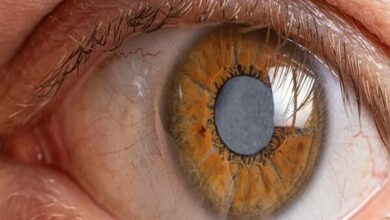

نجات بیمار دیابتی با یک قرص ساده – آژانس خبری Mehr | اخبار ایرانی و جهانی

محققان اخیراً گزارش داده اند كه این دارو به نام لامویدین به نظر می رسد بینش را كه توسط MACO…